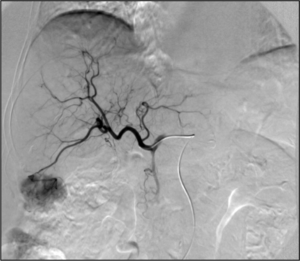

- Angiography: Sometimes referred to as traditional angiography, catheter angiography or digital subtraction angiography (DSA). A small needle is inserted into a blood vessel, then exchanged for a catheter over a wire. The catheter is directed at the vessel to be studied, and contrast is directly injected to evaluate the lumen under video X-ray. This is an older technique than modern CT angiography or MR angiography, but provides unique advantages. With a catheter in place, provocative maneuvers can be performed such as breath holds or instillation of vasodilators, to evaluate a patient's blood flow dynamically. This can reproduce symptoms and identify functional abnormalities in a vessel that a static CT or MR imaging cannot.[84][85] Angiography provides the basis for all endovascular therapy.

- Embolization: The goal of embolization is to decrease or stop flow only in a target vessel, while avoiding cutting off the flow to nearby non-target vessels. This can be performed to stop active bleeding (as in trauma[87]) to limit anticipated blood loss (such as in a complex surgery), or to cut off blood supply to either an abnormal vessel (e.g. aneurysm[88]) or abnormal structure (e.g. tumor). There are many embolic agents available, from metallic plugs and coils to various biologically compatible particles and glues.[89] Depending on the clinical situation, embolization can be temporary or permanent.